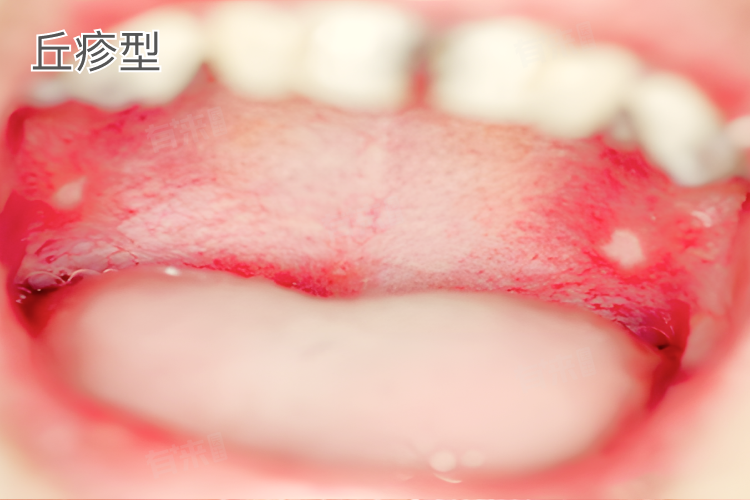

丘疹型

- 在口腔黏膜上出现灰白色的小丘疹,大小如针尖至粟粒般,形状比较规则,多为圆形或椭圆形,常常是多个丘疹聚集在一起,可形成斑块状,看起来就像黏膜表面长出了一小片微微隆起的、质地稍硬的区域,有时表面还会有白色的角质鳞屑覆盖,剥脱后容易留下红色的基底。

- 丘疹多分布在舌背、唇红缘、颊黏膜等位置,一般也不会引起明显疼痛,但会影响口腔黏膜的正常外观和触感。